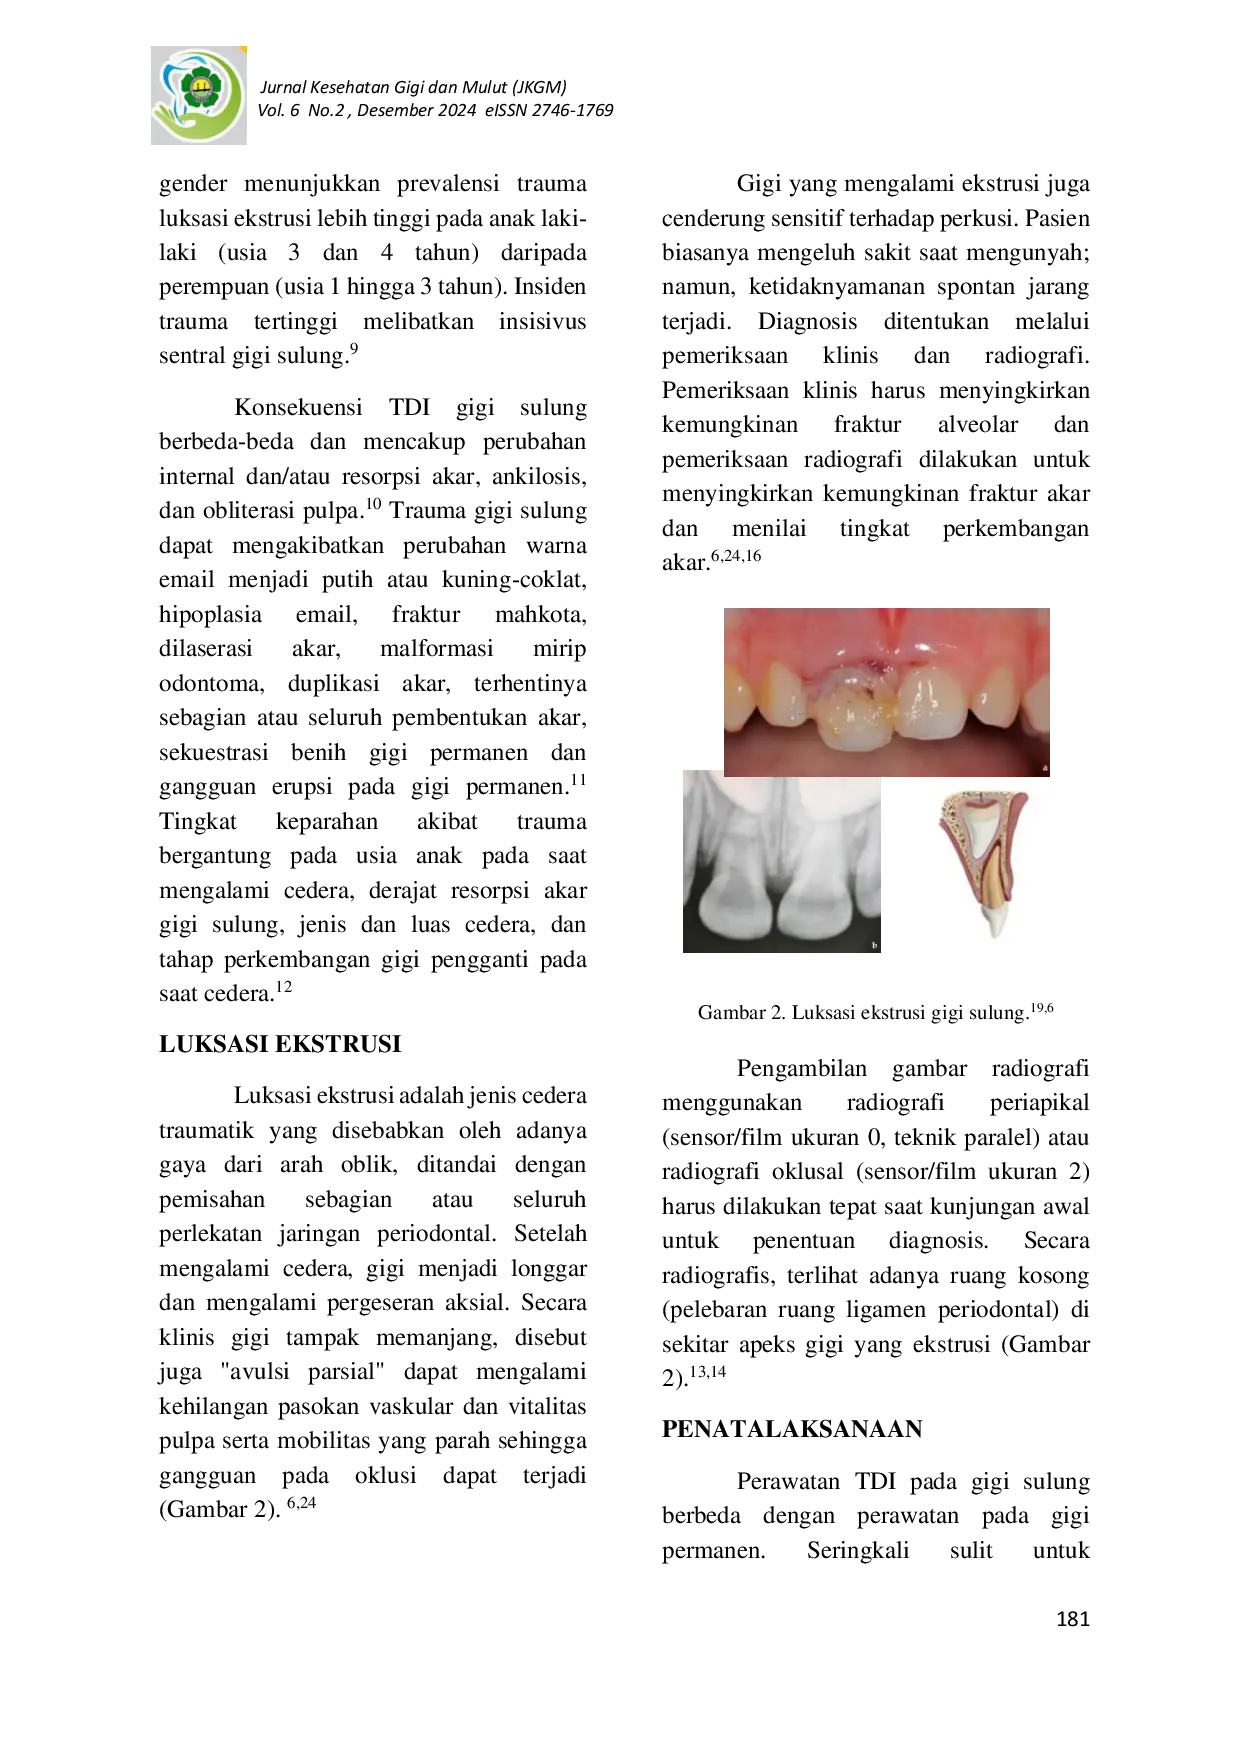

Jurnal Kesehatan Gigi dan Mulut (JKGM)Jurnal Kesehatan Gigi dan Mulut (JKGM)Cedera traumatik gigi (TDI) dan jaringan penyangga merupakan kasus yang sering terjadi pada anak-anak. Sekitar 30-40% anak-anak mengalami trauma pada gigi sulung dengan rentang usia 2 - 6 tahun. TDI pada gigi sulung merupakan ancaman besar bagi kesehatan karena dapat mengganggu fungsi bicara, pengunyahan, estetika, dan erupsi gigi tetap sehingga mengganggu pertumbuhan dan perkembangan gigi serta rahang. Luksasi ekstrusi merupakan salah satu trauma yang sering terjadi, dimana gigi lepas sebagian dari soketnya dan tampak memanjang. Oleh karena itu, penatalaksanaan gigi luksasi ekstrusi pada anak membutukan diagnosis yang tepat, rencana perawatan dan follow-up untuk mendapatkan hasil perawatan yang baik.